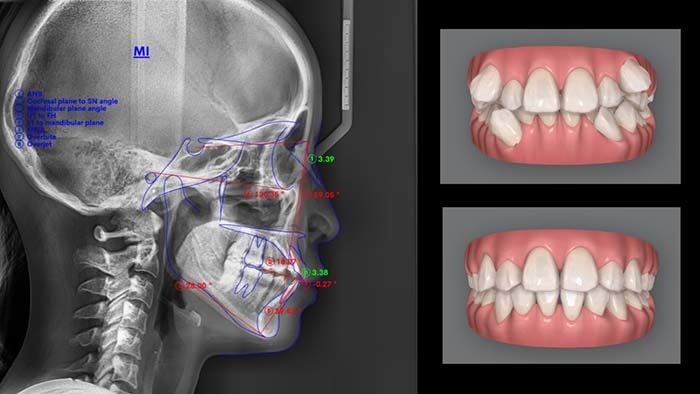

出っ歯(上顎前突)が治った

埋まっている親知らずを抜歯し、出っ歯(上顎前突)をインビザラインで治療した症例です。

16歳

男性

出っ歯が気になる

・マウスピース矯正インビザラインフル/コンプリヘンシブ

18か月・15回